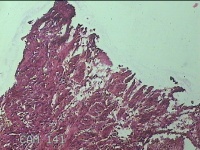

右下腹部切口结节

性别

女

年龄

27岁

临床诊断

皮下结节

一般病史

发现右下腹部切口结节10余年。

标本名称

大体所见

灰白暗红色带皮肤样结节2.3x1.3x0.8cm一个。表面糜烂,切面灰白色,质硬。

需要侵袭性纤维瘤病和纤维瘢痕鉴别一下